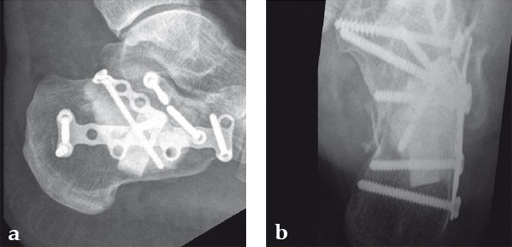

Case 2: A 38-year-old man sustained a lateral tibia plateau fracture (Müller AO Classification 41-B.3/Schatzker type II).

(Case provided by Michiel Verhofstad, Tilburg, The Netherlands)

After opening the lateral wedge, the osteochondral fragment was reduced and maintained with two K-wires. A gap beneath this fragment was left. Subsequently, a 3.2 mm hole was drilled in the lateral wedge using an inside-out technique. Then the lateral fragment was reduced. A 3-hole buttress plate, followed by two subchondral compression screws were used for final fracture fixation. Finally, Norian drillable was injected in the gap through the predrilled hole. Weight bearing was started after 6 weeks. At 6 months the fracture had healed anatomically and the patient was complaint-free.